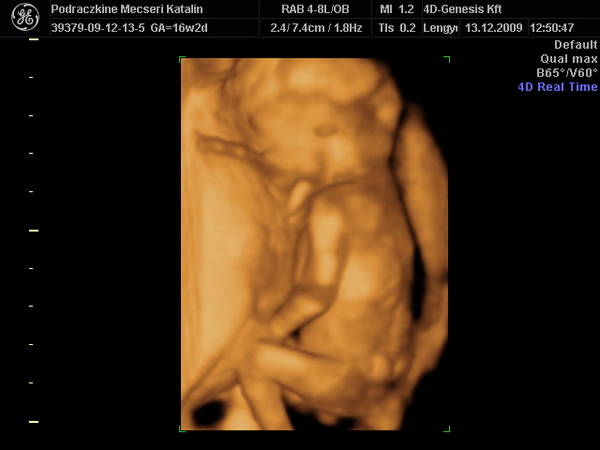

Kép Itt pedig dörzsöli a szemét [/img][/url]